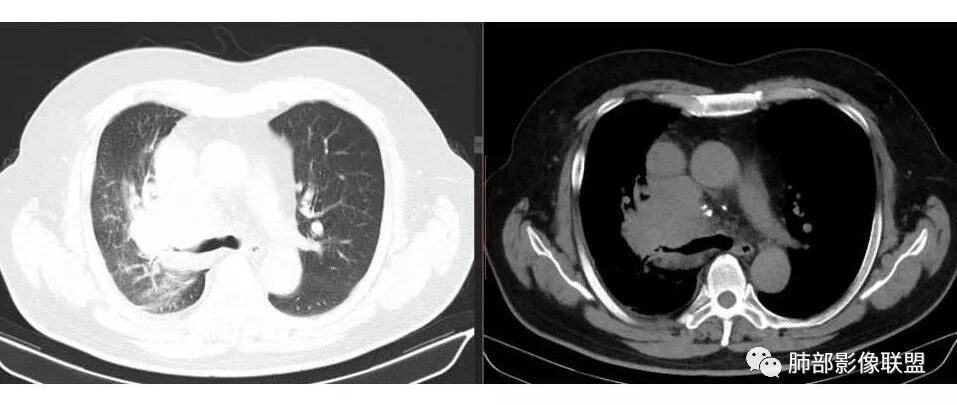

肺门及纵隔多发淋巴结。2L,4R,3区都有肿大淋巴结。

南边:有老师认为,血管前的这个应该是一个胸腺来源的。我觉得不是,为什么不符合胸腺来源呢,就看那个内乳动脉

双侧对比:右侧增粗,提示供血

但在内侧,不是外移

所以我倾向于淋巴结可能

胸腺瘤按理推压外移的多

而且胸腺癌转移不以淋巴结为主,如果淋巴结显著,按理周围侵袭性比较强,淋巴结也应该以附近为主,不应该以肺门为主,不符合引流规律。

南边: 而且肺癌,一定受叶段的局限,这一例跨越右肺门,提示多个淋巴结融合

南边: 例如这个病灶,如果是一个孤立的肿块,边界清晰,提示破坏性不强,不应该是包绕支气管,是推移到一边为主,这个表现为包绕,提示是多个病灶融合